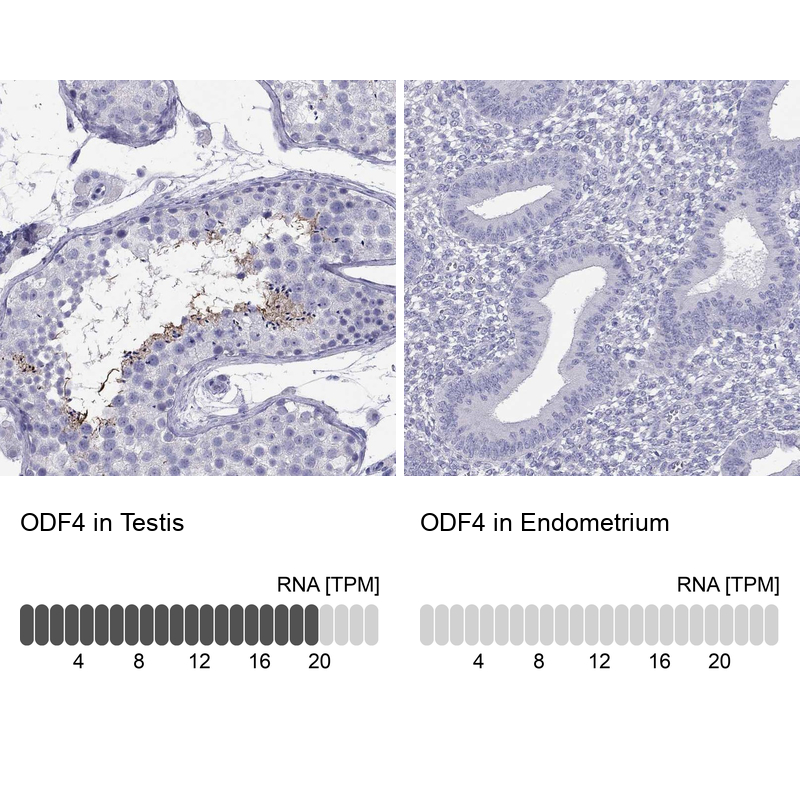

Learn how we validate our antibodies, how we secure their reproducibility, and why we apply enhanced validation. Our antibodies are validated in IHC, ICC-IF, and WB.